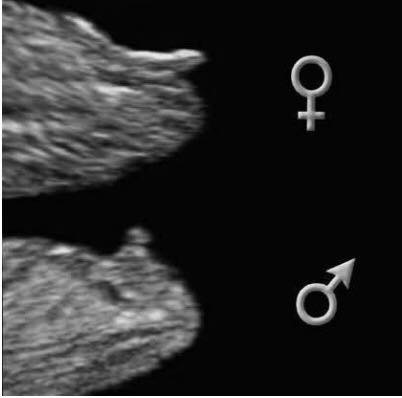

Men nu er jeg lidt i tvivl, om der er en nub på det her billede, eller om det er for tidligt at se den.. Og hvad gætter I på af køn?

Og er der nogle, der kan huske, hvad den der side med gender hedder? Der hvor de skulle være gode til at gætte køn..